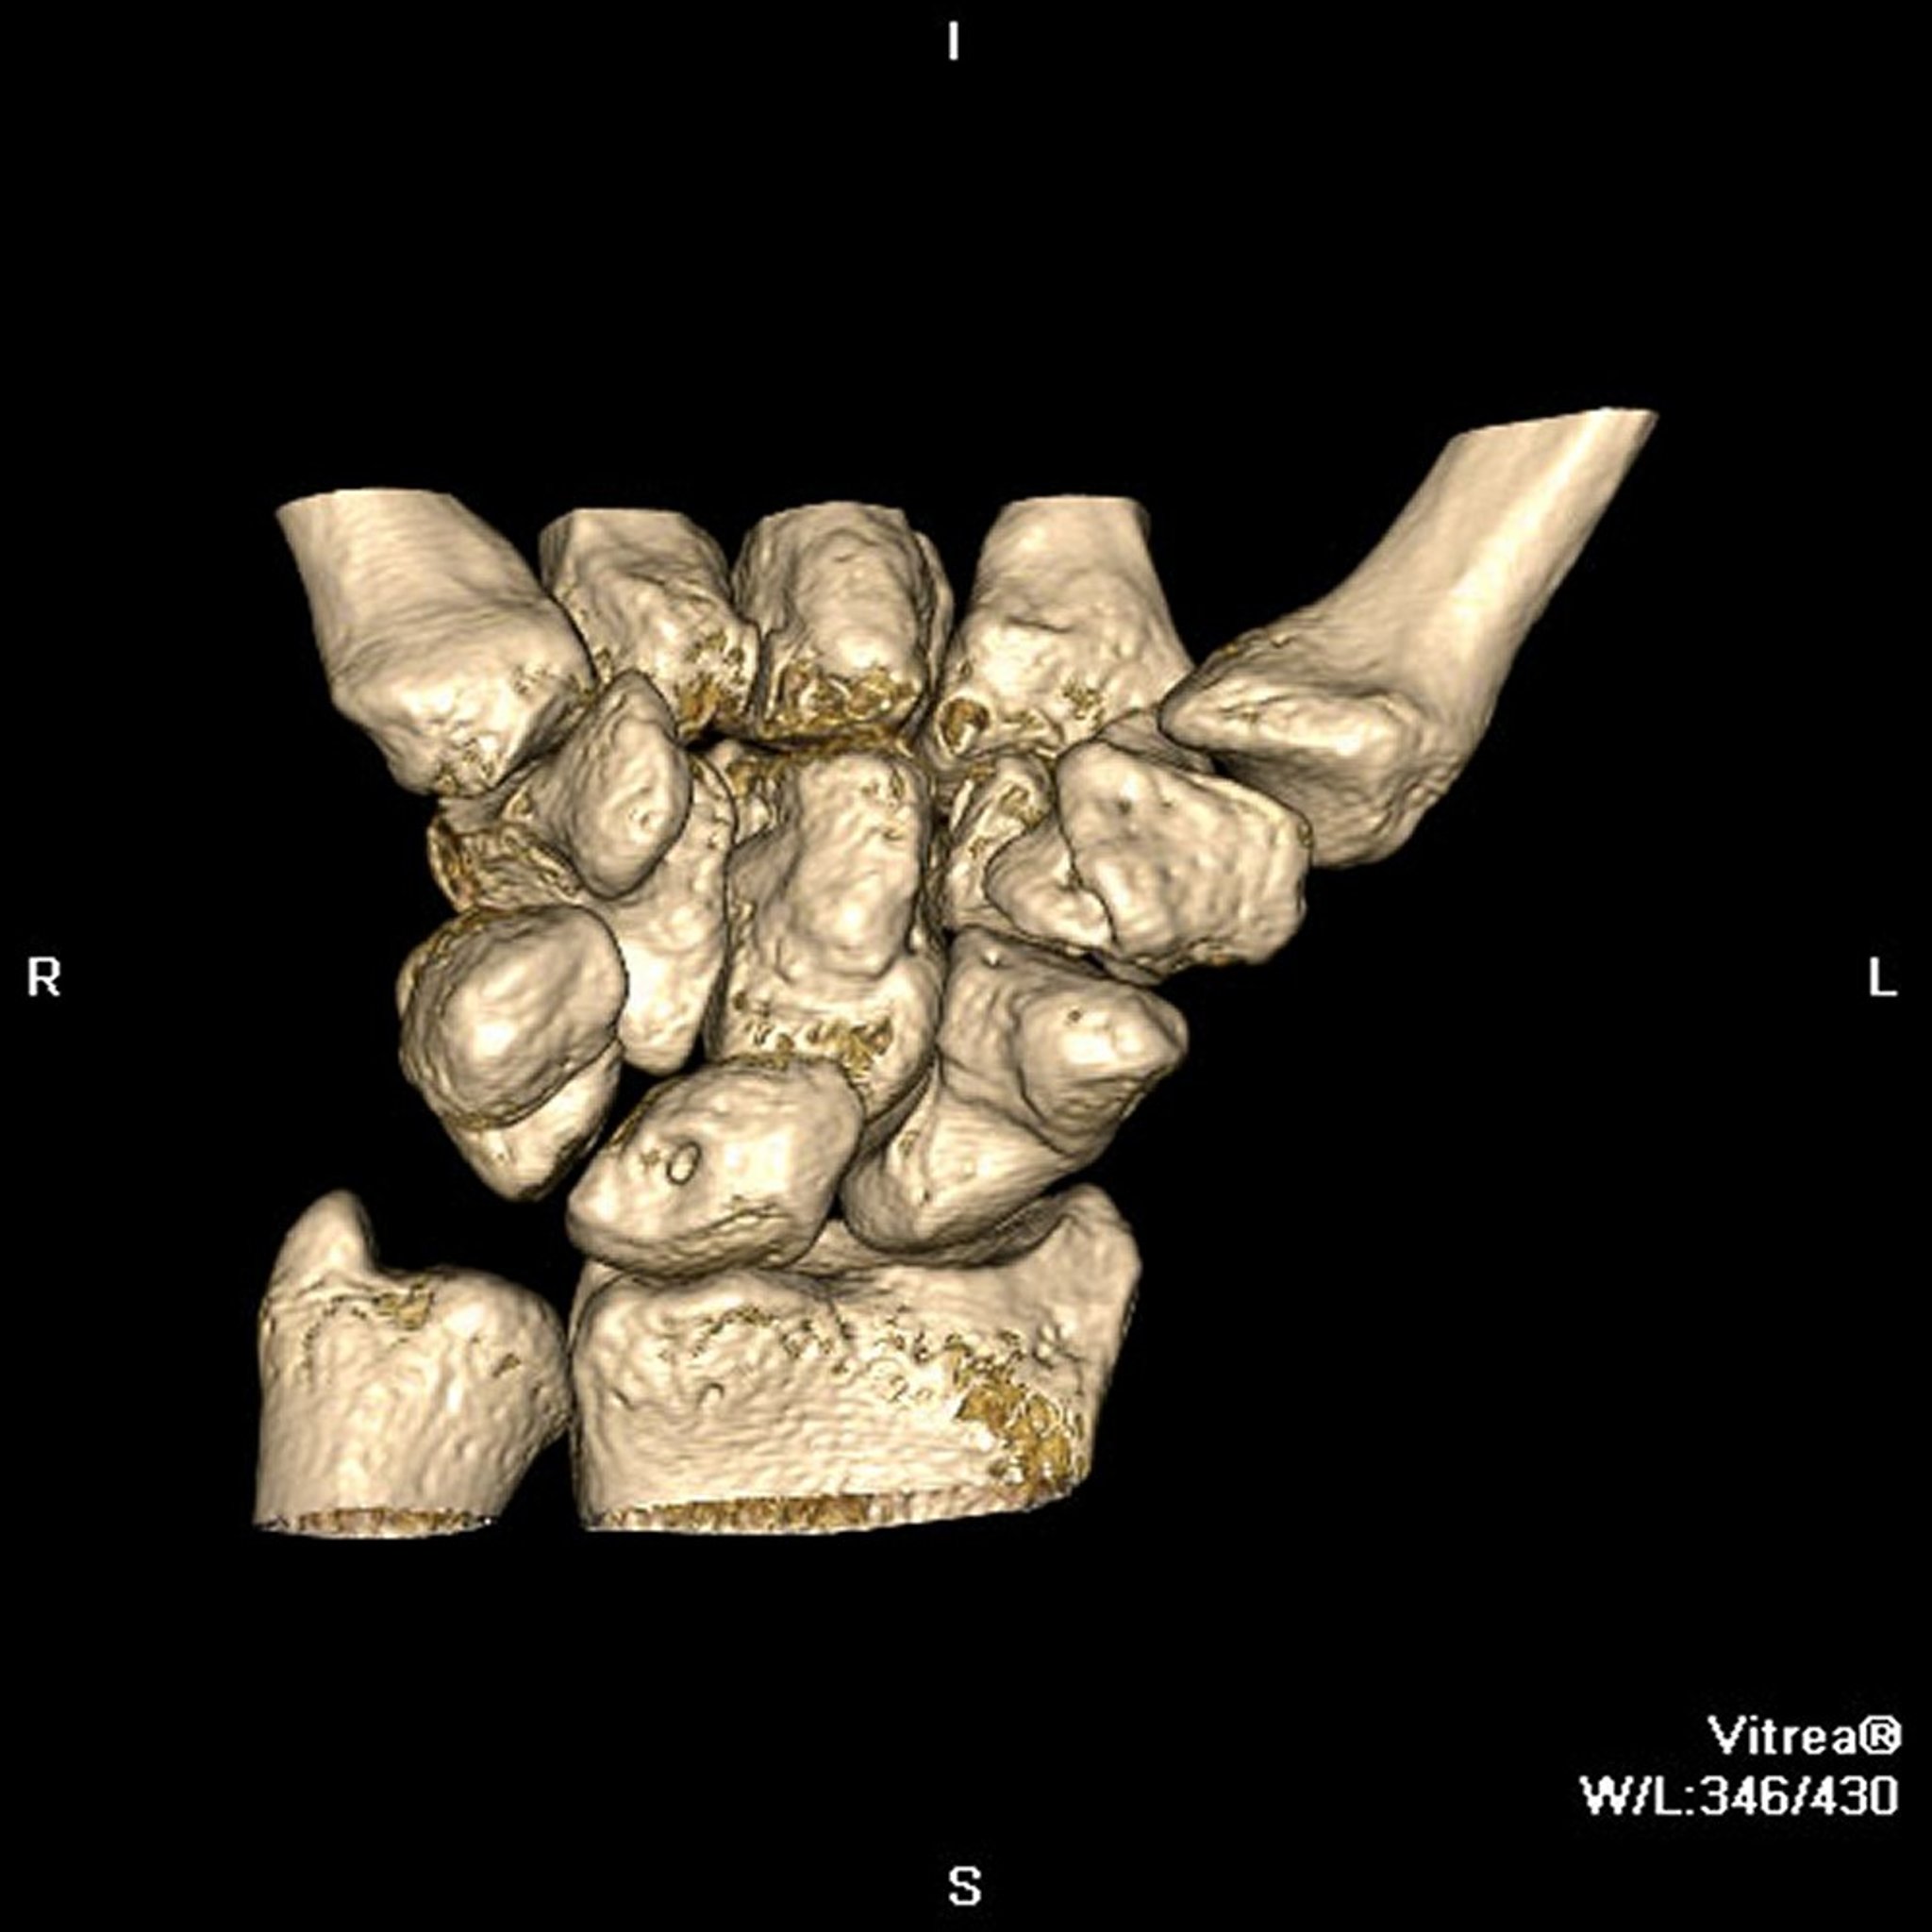

Dalam tomografi terkomputasi (CT), yang dulunya disebut tomografi aksial terkomputasi (computed axial tomography, CAT), sumber sinar-x dan detektor sinar-x merotasi seseorang. Pada pemindai modern, detektor sinar-x biasanya memiliki 4 hingga 64 baris sensor atau lebih yang mencatat sinar-x yang melewati tubuh. Data dari sensor menunjukkan serangkaian pengukuran sinar-x yang diambil dari berbagai sudut mengelilingi orang tersebut. Namun, pengukuran tidak dilihat secara langsung, tetapi dikirim ke komputer. Komputer mengubahnya menjadi gambar yang menyerupai irisan 2 dimensi (penampang melintang) dari tubuh tersebut. Komputer juga dapat membangun gambar 3 dimensi dari gambar yang direkam.

Penggunaan CT

Gambar yang sangat detail memberikan detail lebih lanjut tentang kepadatan jaringan dan lokasi ketidaknormalan dibandingkan sinar-x, sehingga dokter dapat menemukan struktur dan ketidaknormalan dengan tepat. CT memungkinkan penguji untuk membedakan antara berbagai jenis jaringan, seperti otot, lemak, dan jaringan ikat. Dengan demikian, CT dapat memberikan gambar detail organ spesifik yang tidak terlihat pada sinar-x dan lebih berguna untuk pencitraan sebagian besar struktur di otak, kepala, leher, dada, dan perut.